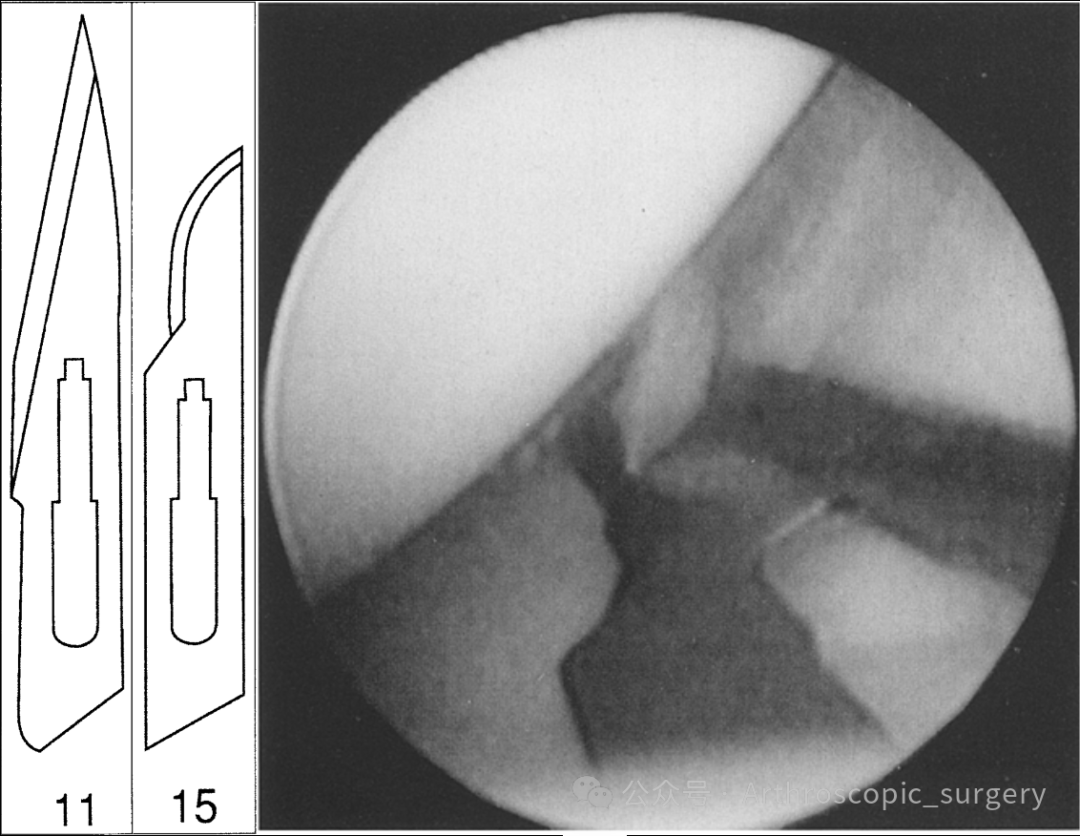

而目前临床上,关节镜运用较多的是11、15号刀片。

但是与15号刀片相比,我们可以看到11号刀片有着较长的刀刃,同时刀刃与刀片过渡时没有明显的陡坡,这样就能避免下图中由于患者关节肌肉紧张或者肥胖时,需要过多的穿刺进关节腔,这种情况下在退出时组织卡压而导致手术刀片遗留在关节腔。

手术刀怎么换刀片骨科精读 | 关节镜切口该用几号刀片?细节要注意好!_https://www.jmylbn.com_新闻资讯_第5张